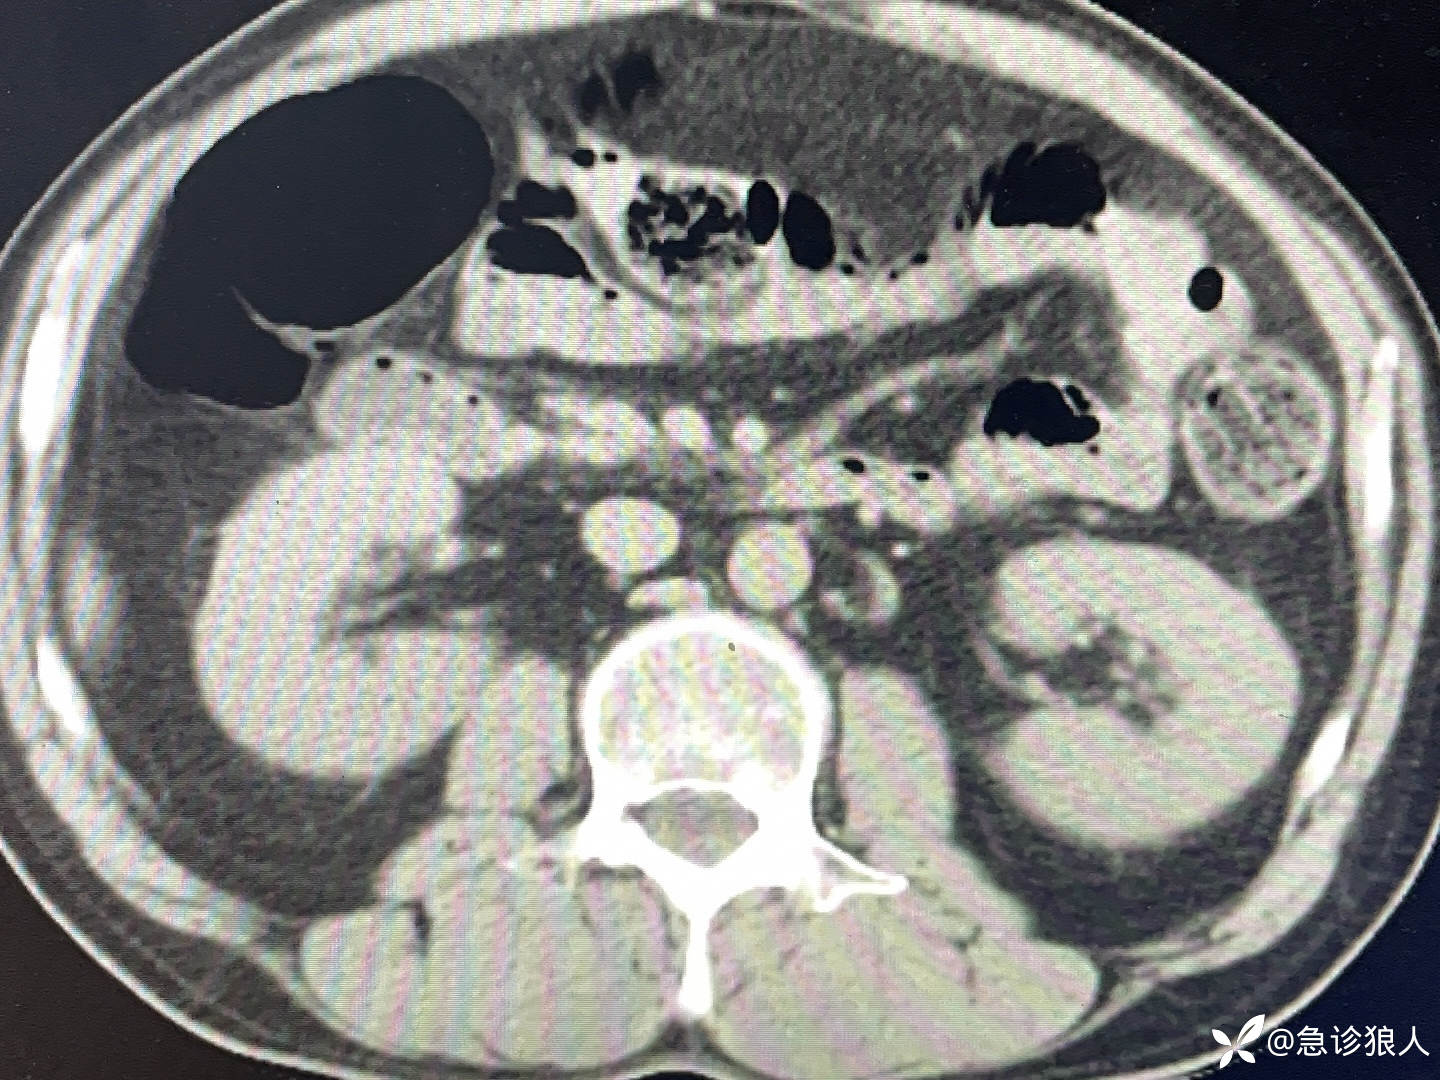

打开患者的强化CT!具体如下:

我提高语速,“重症感染,没找到感染灶,我能看出来的就两个事,胆囊周围渗出增多,但不像胆囊,双肾周围渗出增多,但我顺着看了好几遍,泌尿系我没看到问题!”

几乎在我说完的瞬间,那边传来声音,“你看他的前列腺,低密度灶很多。”

我瞬间把影像停在了患者的前列腺上,我说,“谢谢,老师!”

一位退休返聘的老师正好路过我电脑旁,指着电脑说,“前列腺脓肿!请个泌尿外科会诊!”

我快速汇报完病人情况,泌尿外科医生看着病人的强化CT说,“这不可能是前列腺炎!”